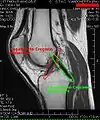

Imaging

MRI

Both anterior cruciate ligament (ACL) and posterior cruciate ligaments (PCL) are hypointense on both T1 and T2 weighted images of MRI. However, some high signal striations are often seen at the distal part of the ACL, making ACL higher intensity than PCL on MRI scans.[17]

Knee MRI (PD TSE FS sagittal)